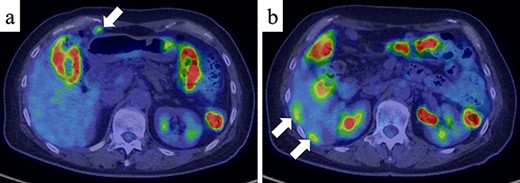

A 61-year-old woman was admitted to our hospital for examination of positive fecal occult blood test. She had a medical history of diabetes but no surgical history. Laboratory data showed that complete blood cell count and hepatic and renal functions were normal. The serum carcinoembryonic antigen level was slightly elevated to 8.7 ng/ml (reference value < 5.0 ng/ml), and the carbohydrate antigen 19-9 level was within the normal range. Colonoscopy demonstrated a Type I tumor with depression and fullness in the ascending colon, and it was VI high grade according to the Kudo pit pattern classification (Fig. 1); tissue biopsy was obtained during colonoscopy. This tumor was diagnosed as adenocarcinoma with massive submucosal invasion. Enhanced computed tomography (CT) revealed numerous nodules throughout the abdominal cavity and a small amount of ascites in the pelvic floor (Fig. 2). Ascending colon cancer could not be pointed out. Positron emission tomography and CT revealed a nodule with mild fluorine-18-fluorodeoxyglucose (FDG) uptake in the peritoneum (maximum standardized uptake value (SUVmax) = 3.0) and two nodules with mild FDG uptake (SUVmax = 3.8 and 4.1) around the liver (Fig. 3). Abnormal FDG uptake that showed the primary tumor was not found. Peritoneal dissemination of the ascending colon cancer was considered among the preoperative differential diagnoses. Based on the degree of the FDG uptake, pseudomyxoma peritonei was also differentially diagnosed.

Positron emission tomography and CT (PET/CT) (a) PET/CT showed a nodule with mild FDG uptake in the peritoneum (SUVmax = 3.0) (white arrow). (b) Two nodules with mild FDG uptake (SUVmax = 3.8 and 4.1, respectively) were confirmed around the liver (white arrows).